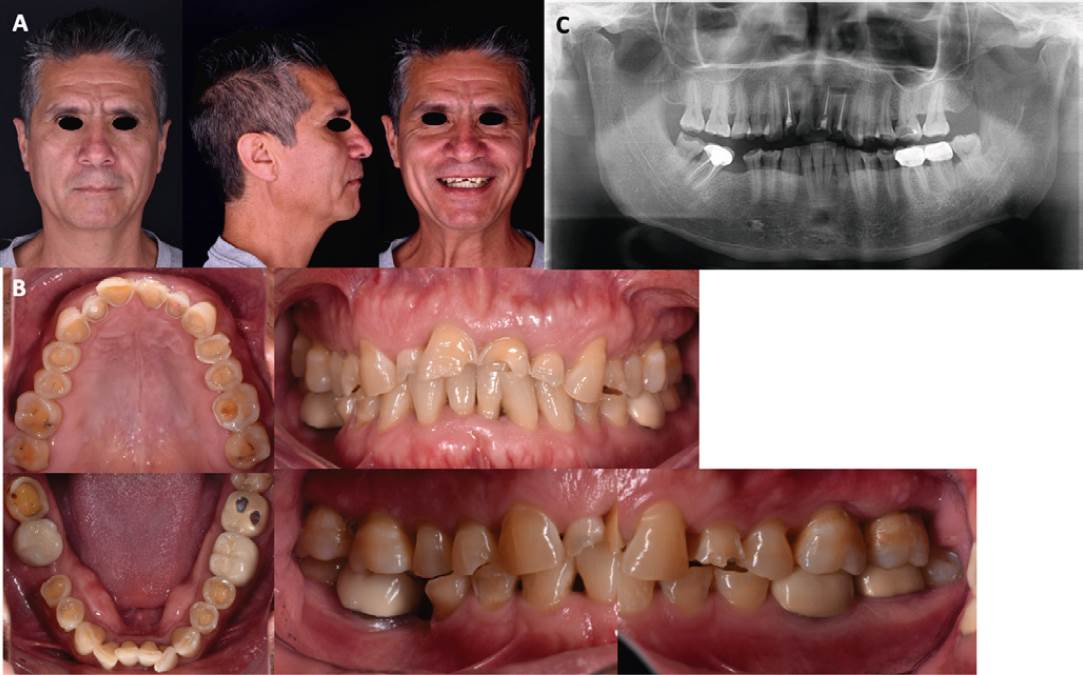

Paciente masculino de 53 años de edad, cuyo motivo de consulta fue “Quiero arreglar mis dientes”. Al efectuar el análisis extraoral presentó un biotipo facial dolicocéfalico con perfil convexo. Los tercios faciales fueron simétricos, labios delgados, no presentó exposición dental con labios en reposo, presentó una sonrisa baja (Figura 1.A). En el análisis intraoral los arcos dentales presentaron una forma ovoide, la línea media desviada 1mm a la derecha, banda de encía ancha queratinizada de 5mm, los ejes longitudinales se encontraron en posición armónica, erupción pasiva de los dientes 12, 21 y 22, así como poco remanente dentario. Se observó pérdida de substancia dentaria por una combinación de atrición y biocorrosión en las caras oclusales y palatinas de todos los dientes maxilares, así como en el diente 47, y premolares mandibulares, estos últimos con abfracciones, erupción pasiva en los dientes 42, 41 y 31 (Figura 1.B). En la ortopantomografía no presentó patologías, se observaron restauraciones en molares y tratamiento de conductos en dientes maxilares anteriores (Figura 1.C).

Figura 1 Estudios iniciales. A. Fotografías extraorales de frente, perfil y sonrisa. B. Fotografías intraorales, en las que se observa desgaste severo generalizado de las caras oclusales, así como lesiones cervicales no cariosas como abfracciones. C. Ortopantomografía.